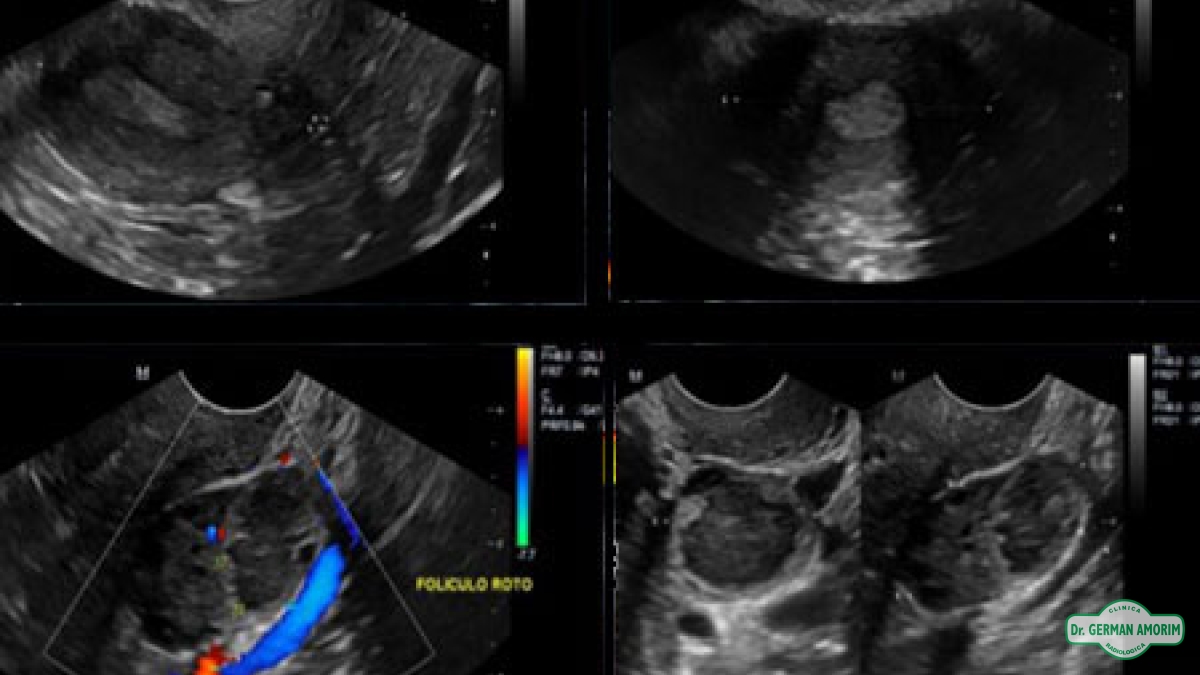

Ovarios: se observa la cantidad de folículos de cada ovario y el crecimiento de los mismos. Cada folículo del ovario va creciendo a lo largo del ciclo, hasta romper ( 19 a 23mm.) al momento de la ovulación y expulsar el o los óvulos.

Ecográficamente, si se produce la ovulación se visualizan signos directos de la misma, que sería la desaparición del folículo o el aplanamiento e irregularidades de la pared del mismo y signos indirectos como la presencia de líquido en el fondo de saco de Douglas.